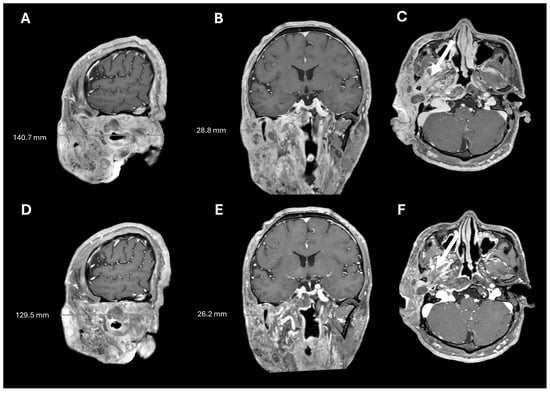

Figure 2.

Pre- and post-operative brain MRIs. Pre-operative T2, T1, and T1+contrast imaging (A–C), showing a large, T2-hyperintense, enhancing, predominantly right facial mass. Post-operative T2, T1, and T1+contrast imaging (D–F), showing posterior tumor debulking (arrows).

A 38-year-old man with genetically confirmed NF1 and a large conglomerate R facial PN, with status post debulking at age 8, presented to our institution for further management of his disfiguring PN. His family history was positive for NF1 in his mother and daughter. Genetic testing revealed a heterozygous pathogenic truncating variant in exon 38 of NF1: c.5438C>A and p.Sesr1813Ter. No reportable variants were found in SPRED1. Neurological examination showed a large right facial mass (Figure 1A), >6 café au lait macules—all >15 mm in size, axillary freckling, and numerous cutaneous neurofibromas. A brain MRI demonstrated a right predominantly facial PN (Figure 2A–C). Following posterior auricular tumor debulking, a brain MRI showed an interval reduction in the tumor size posterior to his ear (Figure 2D–F). Pathological examination showed positive S100, SOX-10, and CD34, and negative SMA, consistent with neurofibroma (Figure 3). Ki-67 was less than 1%. Molecular analysis identified a pathogenic variant (NM_000267.3: c.5438C>A, p.Ser1813Ter) in the heterozygous state in NF1. At the time of diagnosis, there were no FDA-approved agents for adult NF1 PNs. On the basis of the higher reported ORR in selumetinib compared to mirdametinib, selumetinib was the targeted agent selected for our patient. However, no head-to-head clinical trials have directly compared mirametinib and selumetinib. He was administered 25 mg/m2 (40 mg BID) selumetinib, which was complicated by a facial acneiform rash and asymptomatic elevated Grade 3 CPK after 1 month. His rash resolved with topical adapalene 0.1%/benzoyl peroxide 2.5% gel, and his CPK improved to Grade 1 with a dose reduction in selumetinib to 35 mg BID. At 7-month follow-up, a reduction in tumor burden was noted clinically (Figure 1A–C), with a corresponding reduction in tumor volume radiographically (Figure 4A–F). On his brain MRI, the pre-selumetinib tumor volume was 284.65 cm3 and the post-selumetinib tumor volume was 236.92 cm3, showing a 16.77% reduction in tumor volume. Given the infiltrative nature of the tumor, volume was calculated using an ellipsoid volume formula of 0.5 × length × width × height. At time of publication, he remains on selumetinib and endorses improvement in quality of life (QoL).